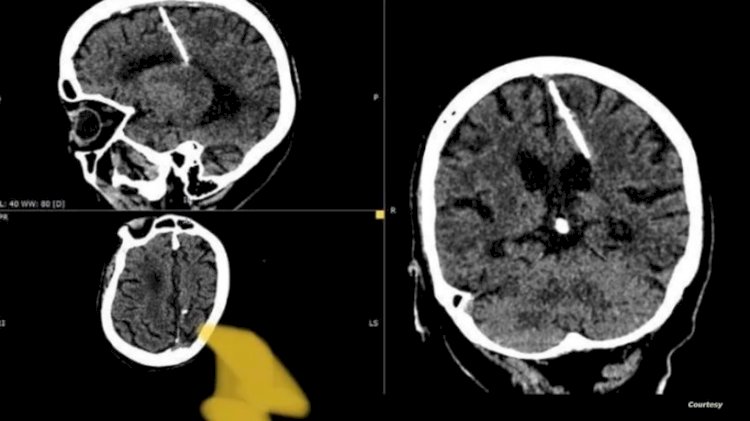

عثر أطباء خلال فحص بالتصوير المقطعي على إبرة بطول ثلاثة سنتيمترات موجودة منذ ثمانين عاماً داخل دماغ امرأة مسنّة في أقصى الشرق الروسي.

وقالت إدارة الصحة المحلية لقد اخترقت الإبرة الفص الجداري الأيسر، لكن لم يكن لها التأثير المقصود، إذ نجت الفتاة.